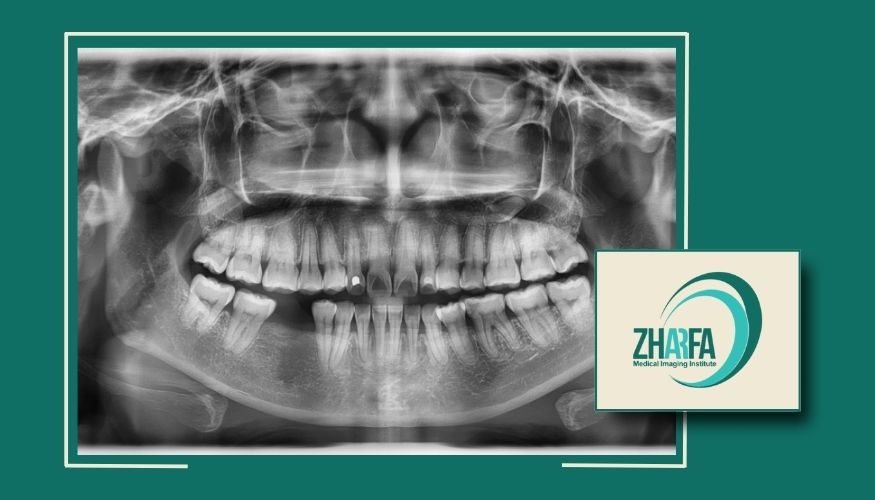

عکس OPG: برای نمایش وضعیت کلی فک و دندانها در یک تصویر.

نحوه انجام رادیوگرافی پانورامیک دندانها